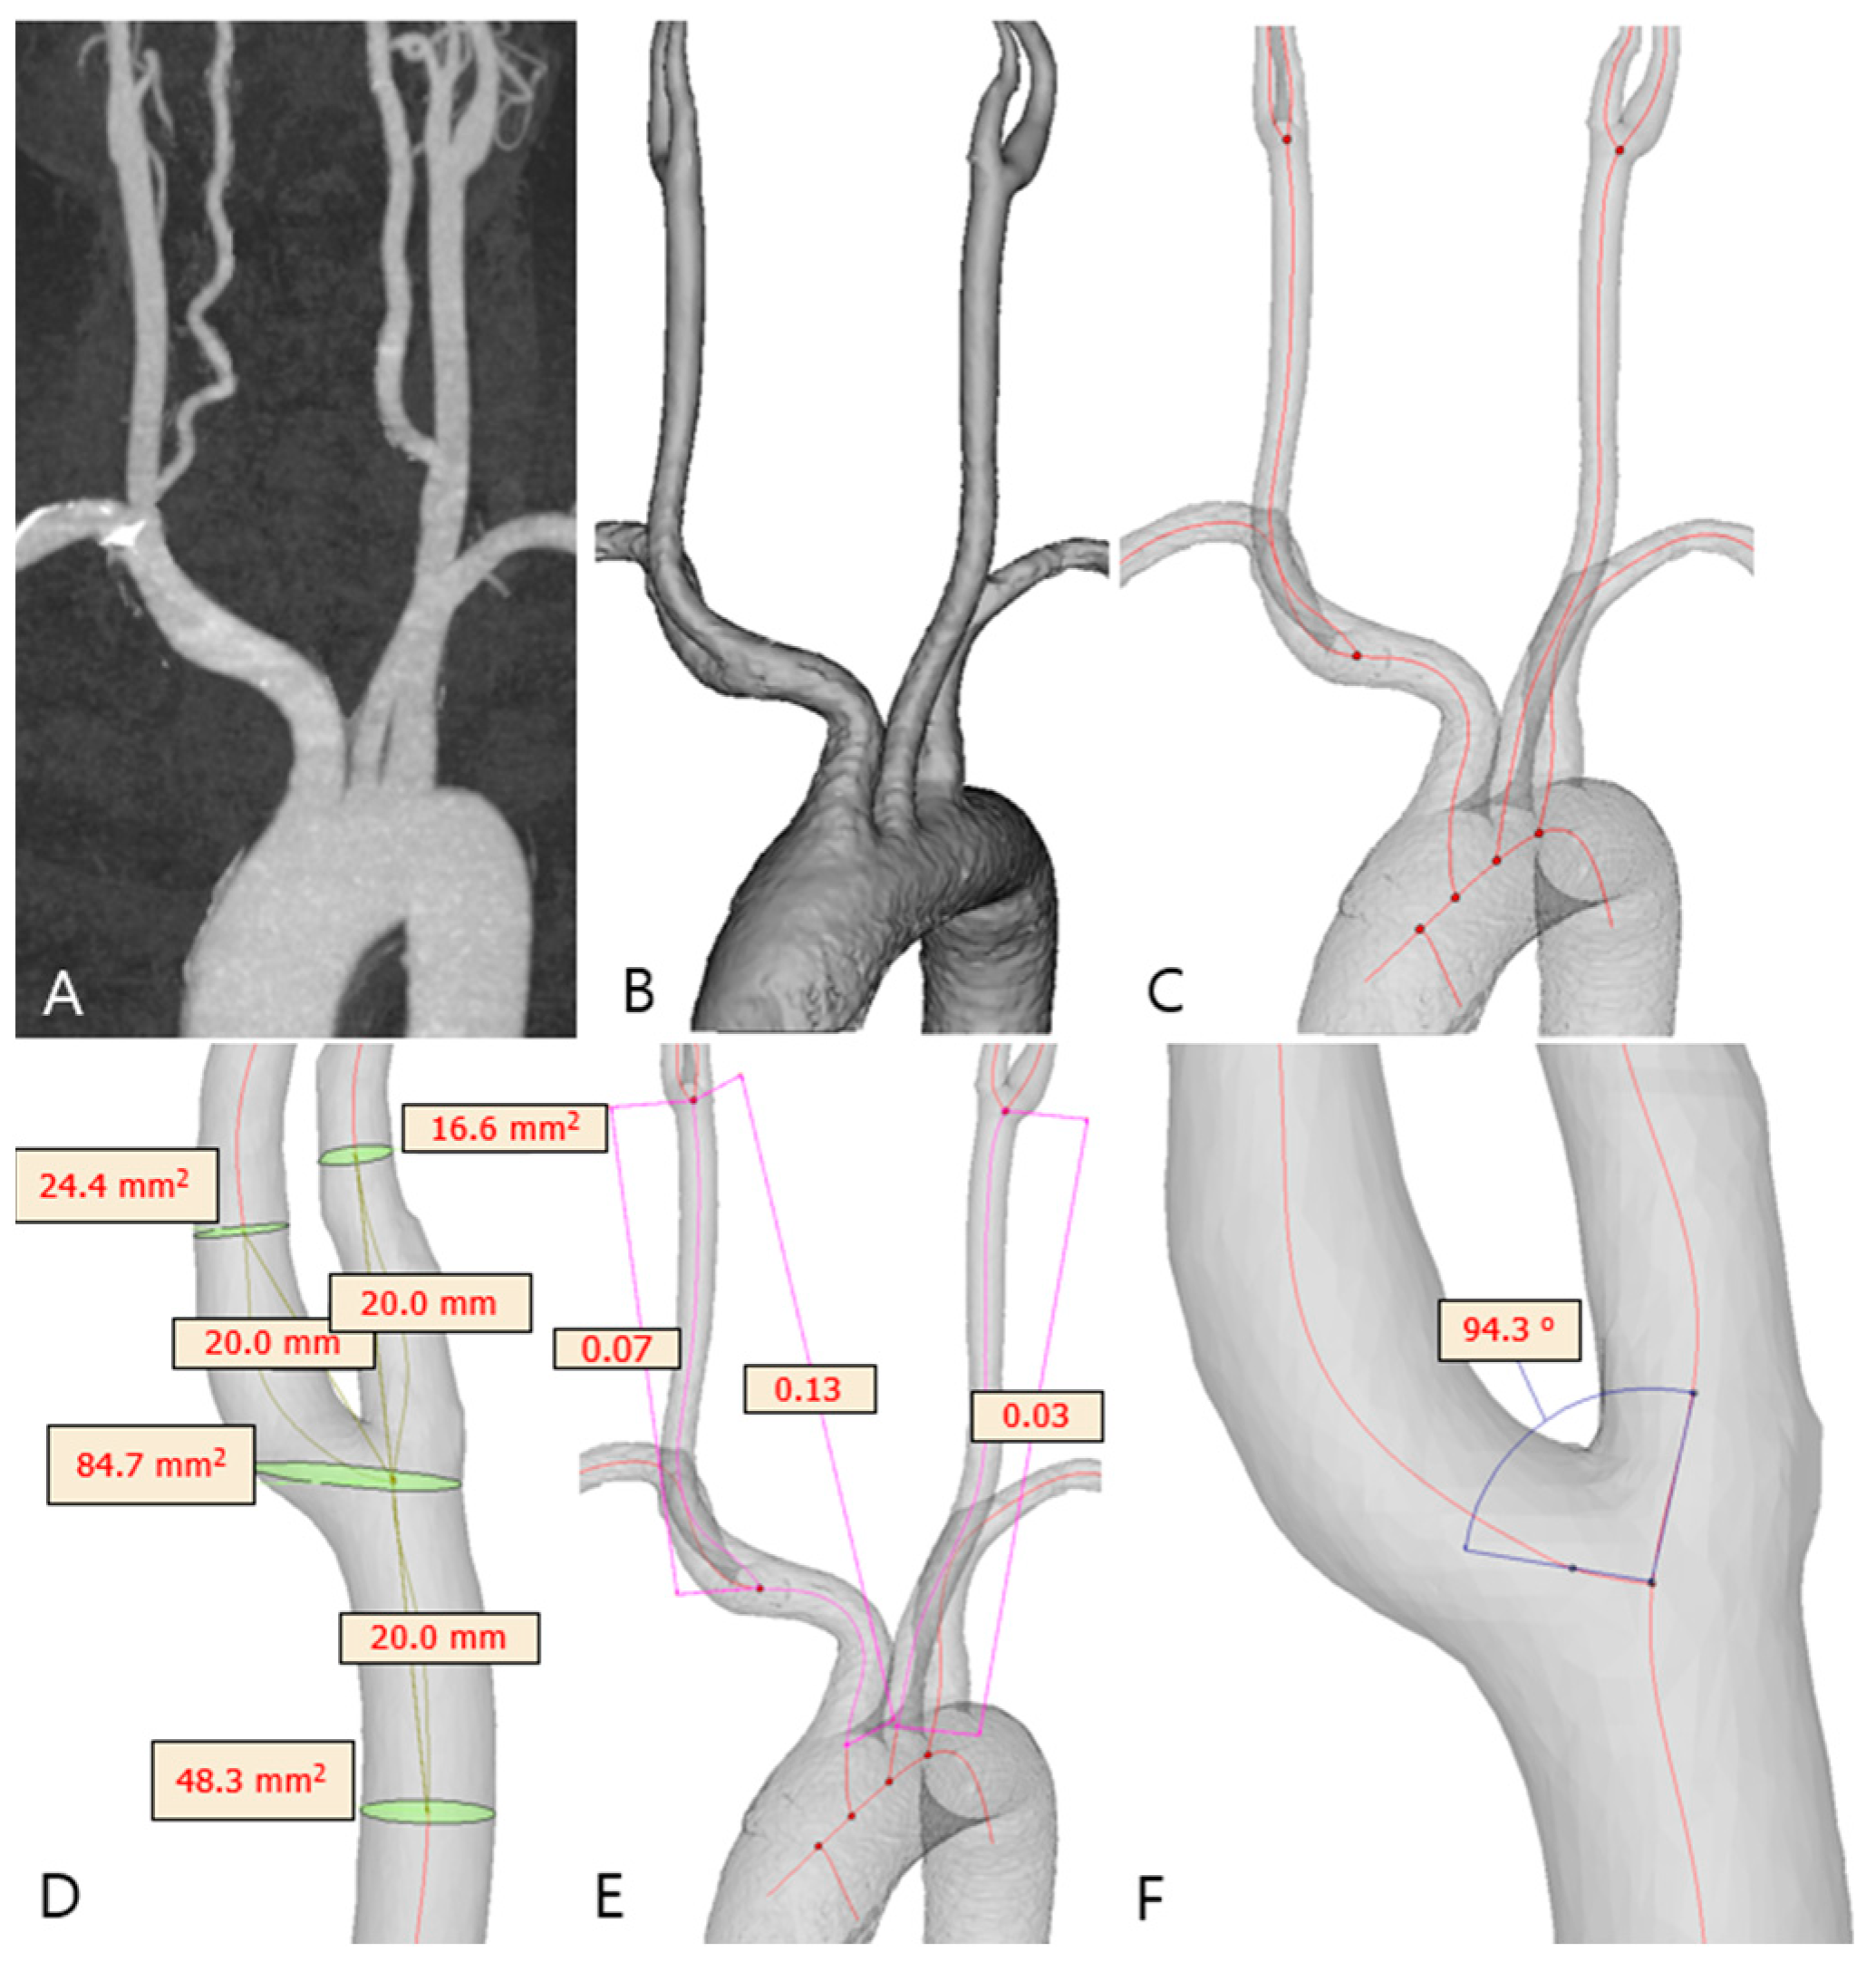

2.3. Carotid Artery 3D Model Reconstruction

2.4. Carotid Geometry Measurement